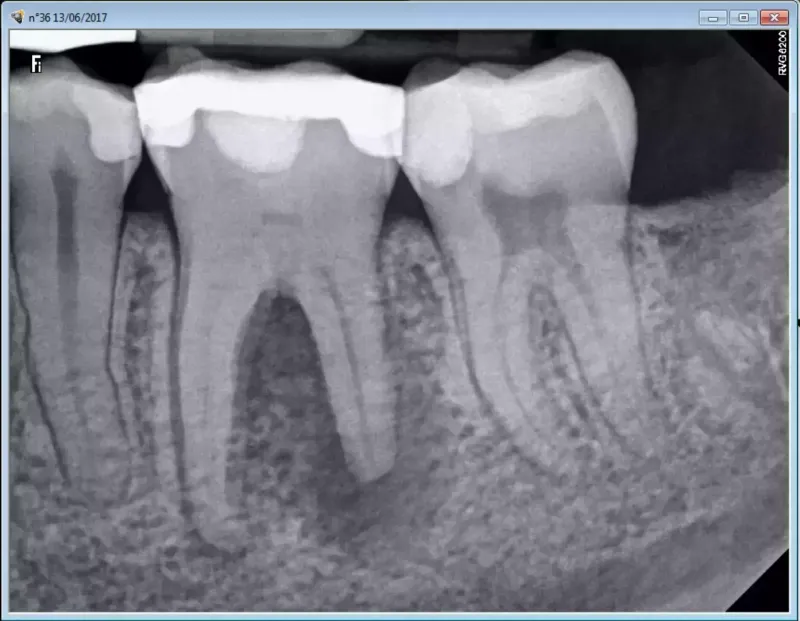

The primary driver of safety when discussing are dental X-rays safe is the sensitivity of the receptor. Modern digital sensors require significantly less "dwell time" (exposure time) than the old silver-halide films used decades ago. If you are interested in the broader infrastructure of dental diagnostics and how clinics manage these maintenance stages, you can look into this data:

Beam Filtration: The use of aluminum filters to remove "soft" X-rays that don't contribute to the image but add to the skin dose.

Voltage Calibration: Ensuring the kilovoltage (kVp) is high enough to penetrate the bone but low enough to maintain contrast.

Sensor Efficiency: The leap from CCD to CMOS technology has halved the required radiation for a clear diagnostic image.